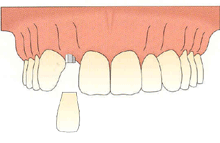

什么是種植牙 ?種植牙,也叫人工種植牙,并不是真的種上自然牙齒。

它是將與人體骨質(zhì)兼容性高的生物材料(一般稱(chēng)作種植體)植入牙槽骨中,然后在種植體上做出假牙的一種修復(fù)方式。

在牙槽骨中的種植體就相當(dāng)于我們自然牙的牙根,它可以和牙槽骨緊密地生長(zhǎng)成一體,所以能夠穩(wěn)穩(wěn)地支撐并固定上部的假牙。